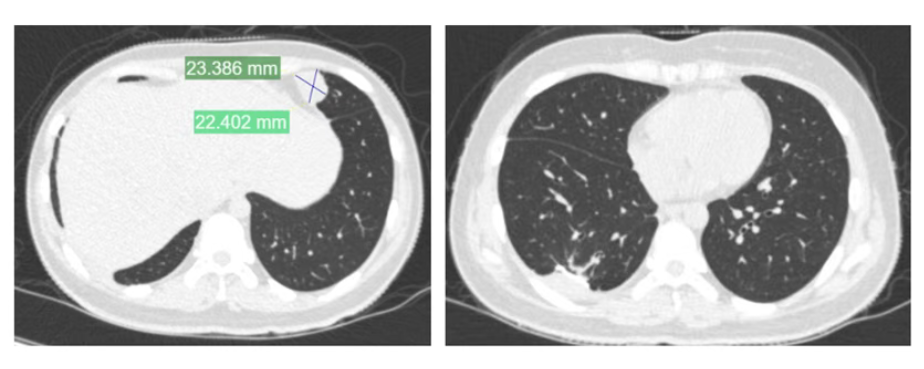

夏夏前期接受了术前化疗、截肢手术及术后化疗,使用的是一线化疗方案。然而,结疗不到一年,肺部出现转移病灶,这种情况是恶性肿瘤的普遍特性,骨肉瘤患者中并不少见,尤其是结疗后2年内,是转移和复发的高发期。

为帮助她巩固疗效并延长无病生存期,2024年2月,夏夏经过手术切除后未再进行化疗。术后5个月,左肺再次发现新发转移病灶。2024年11月,夏夏接受胸腔镜下右肺下叶切除术。2025年1月复查:右肺术后改变好转。